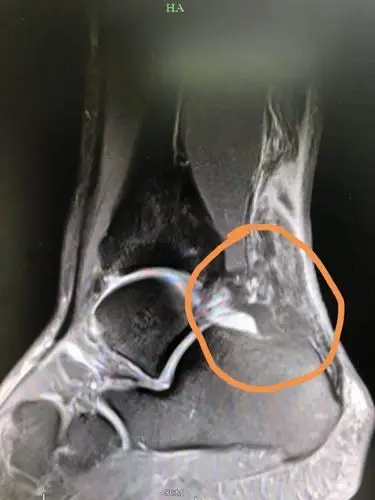

杭州33岁小伙儿连打四天羽毛球后,"脚筋"断了